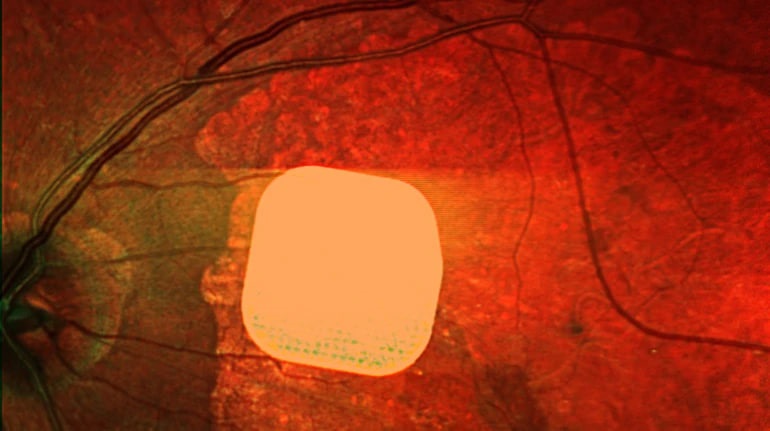

Британські лікарі з лондонського клініки Moorfields Eye Hospital спільно з європейськими колегами провели дослідження з використанням нового електронного імпланту Prima, який допомагає пацієнтам із макулодистрофією, що призводить до втрати зору після 50 років, частково відновити зір. Мікрочип розміром 2×2 міліметри встановлюють під сітківку ока, а пацієнту також під’єднують систему окулярів доповненої реальності з камерою і мінікомп’ютером. Камера отримує зображення, перетворює його на сигнал для мікрочипу, який активує клітини сітківки, а потім сигнал передається до мозку через зоровий нерв. У дослідженні взяли участь 38 пацієнтів із важкими зоровими порушеннями, і після операції 84% з них знову змогли розрізняти літери, цифри та слова. Лікарі стверджують, що ця технологія відкриває нові можливості для людей із важкими зоровими проблемами, допомагаючи підвищити їхню якість життя та незалежність.